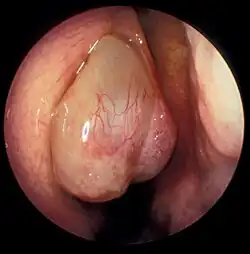

Nasal polyps can be seen on physical examination inside of the nose and are often detected during the evaluation of symptoms. On examination, a polyp will appear as a visible mass in the nostril.[5] Some polyps may be seen with anterior rhinoscopy (looking in the nose with a nasal speculum and a light), but frequently, they are farther back in the nose and must be seen by nasal endoscopy.[12] Nasal endoscopy involves passing a small, rigid camera with a light source into the nose. An image is projected onto a screen in the office so the doctor can examine the nasal passages and sinuses in greater detail. The procedure is not generally painful, but the person can be given a spray decongestant and local anesthetic to minimize discomfort.[13]

There are two primary types of nasal polyps: ethmoidal and antrochoanal. Ethmoidal polyps arise from the ethmoid sinuses and extend through the middle meatus into the nasal cavity. Antrochoanal polyps usually arise in the maxillary sinus and extend into the nasopharynx and represent only 4–6% of all nasal polyps.[7]

However, antrochoanal polyps are more common in children comprising one-third of all polyps in this population. Ethmoidal polyps are usually smaller and multiple while antrochoanal polyps are usually single and larger.[7]